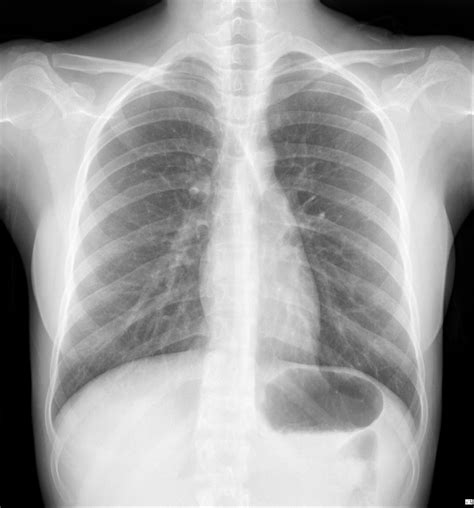

Receiving news of an abnormal chest X-ray can be an unsettling experience, often triggering immediate anxiety about what it means for your health. A chest X-ray is one of the most common diagnostic imaging tests performed in medicine, providing a detailed snapshot of your heart, lungs, airways, blood vessels, and the bones of your spine and chest. When a radiologist identifies something that does not fit the standard pattern of a "clear" or "normal" scan, they classify it as abnormal. However, it is crucial to understand that an abnormal chest X-ray is not a definitive diagnosis of a disease; rather, it is a finding that requires further investigation and clinical correlation by your healthcare provider.

An abnormal chest X-ray simply indicates that the image shows something unexpected or different from the typical anatomy. Because X-rays use ionizing radiation to create images, they rely on differences in density to create contrast. Denser structures, like bones, appear white, while air-filled structures, like healthy lungs, appear dark. When a shadow, spot, or change in structure appears where it shouldn't, or where a normal structure is distorted, the result is flagged.